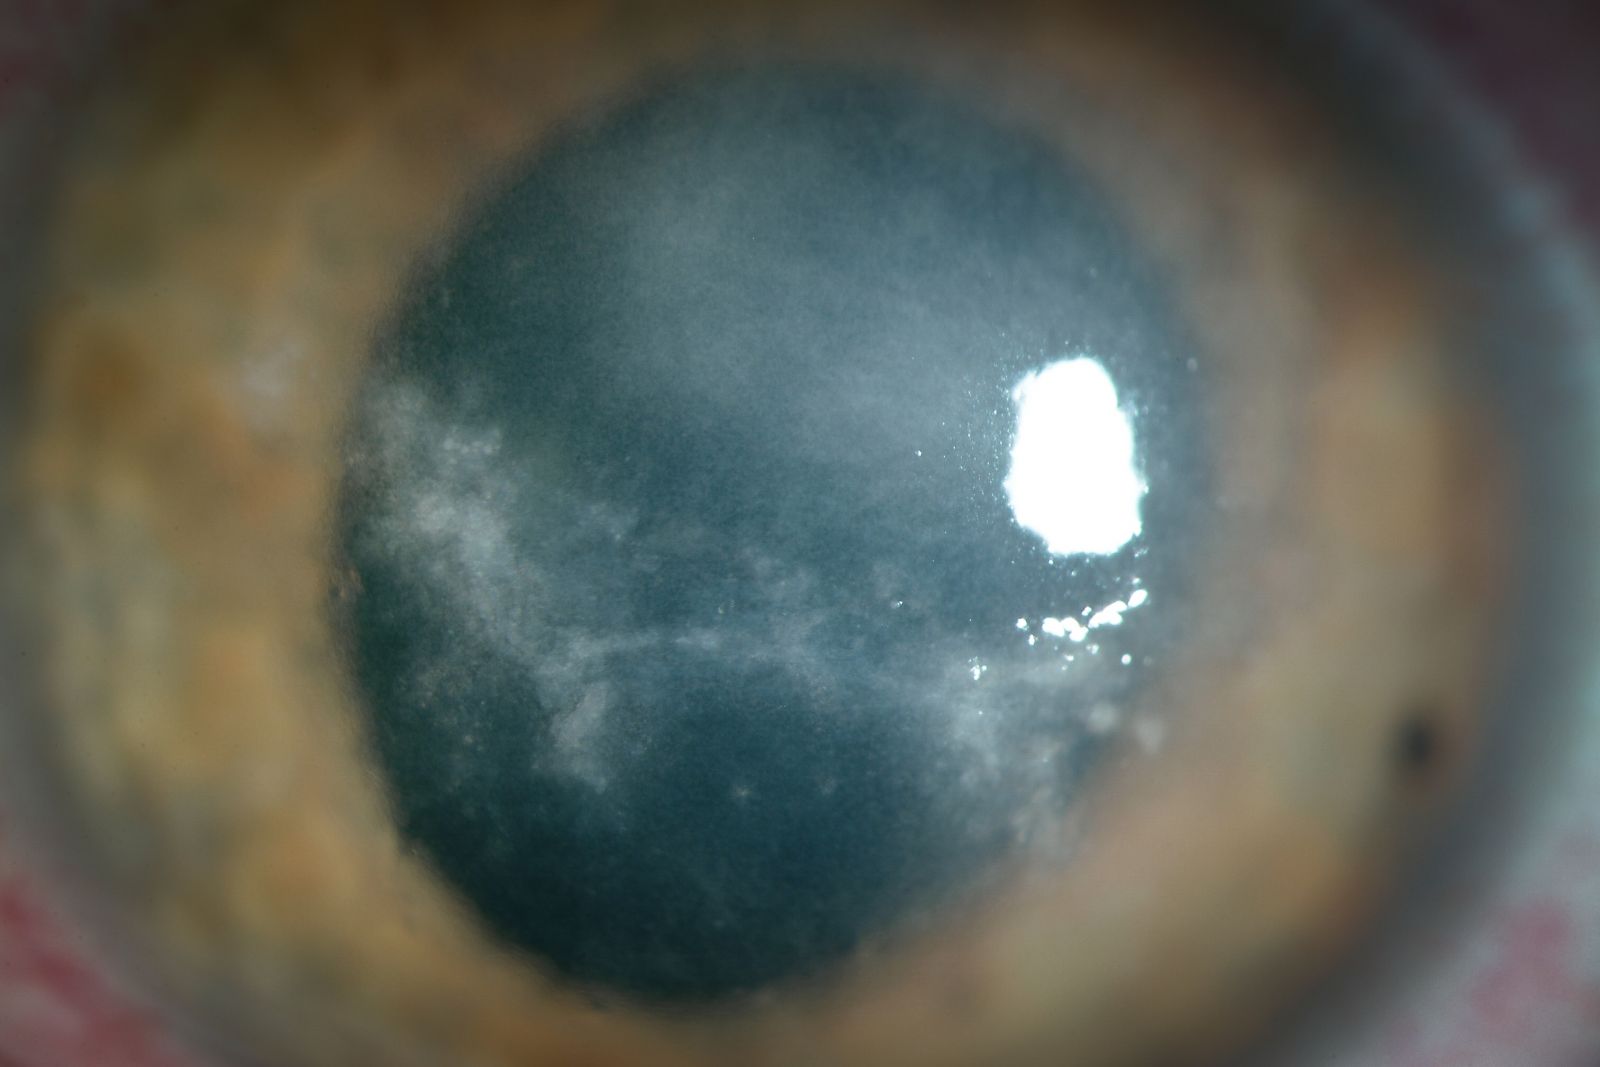

Descripción del caso

Mujer de 17 años que acude por dolor ocular y disminución de visión en OI de tres meses de evolución. La paciente es portadora de lentes de contacto de recambio mensual y ha recibido diferentes tratamientos durante ese tiempo que incluyen antibióticos y antivirales tópicos y, de forma continuada, corticoides tópicos. La exploración biomicroscópica muestra placas de epitelio rarefacto de aspecto edematoso en área corneal central e infiltrado inflamatorio estromal anterior en zona paracentral superior de la córnea. No hay defecto epitelial ni signos de ulceración corneal.Ante la imagen fotográfica de este caso cual es la respuesta correcta:

Los infiltrados adenovíricos clínicamente tienen una morfología característica y son, con frecuencia, bilaterales1. Sin ese aspecto típico y sin otros datos clínicos o de laboratorio, un infiltrado epitelial no puede ser etiquetado como adenovírico. El dolor ocular desproporcionado en relación a los signos oftalmológicos en la queratitis por acanthamoeba puede ser debido a espasmo ciliar o a queratoneuritis y es tan frecuente en esa infección que su presencia en una queratitis como la que muestra la imágen debe de hacer sospechar dicho diagnóstico2.

En el caso de la fotografía se detectaron acanthamoebas en el agar sin nutriente con E. coli en 72h, lo cual proporcionó una estimación indirecta de la carga microbiana de la córnea. El caso ha evolucionado a la opacificación corneal y actualmente se encuentra en fase de secuelas sin que haya signos de infección. El retraso en el diagnóstico y en la administración del tratamiento adecuado empeora el pronóstico visual de estos pacientes. La aplicación continuada de corticoides tópicos favorece la multiplicación microbiana y la penetración del parásito en el estroma corneal3.

Los diagnósticos clínicos de presunción, como el de “infiltrado adenovírico atípico” o queratitis herpética, pueden llevar a errores de seguimiento continuados especialmente si los controles oftalmológicos sucesivos los realizan diferentes oftalmólogos. Ante un caso como el descrito sería más apropiada una descripción de la lesión como “epiteliopatía no filiada asociada a lentes de contacto” y bajo esa premisa aplicar las técnicas diagnósticas que procedan. Un tratamiento empírico en una epiteliopatía corneal no filiada, no debería incluir cortocoides tópicos excepto en ciertas condiciones excepcionales y aplicados con un criterio clínico específico.